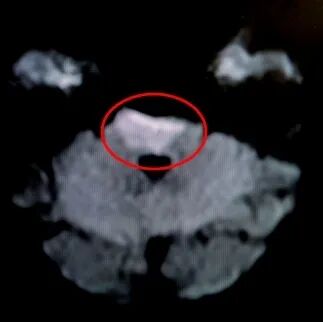

行头颅MRI示:脑桥腹侧梗死。

院前MRI+DWI示:脑干梗死(红圈处所示)。